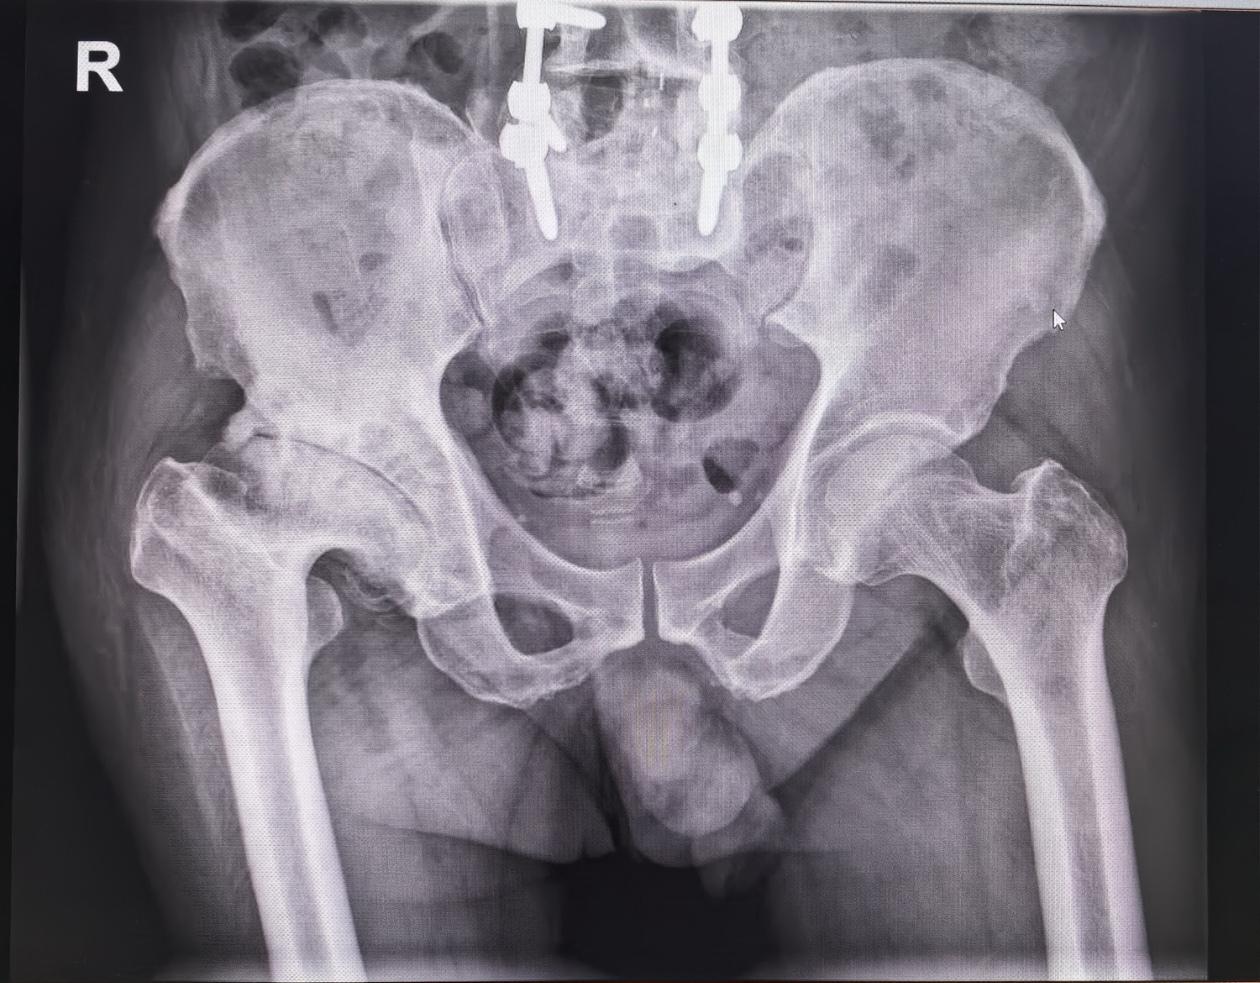

髋关节翻修。髋关节置换术后22年,假体磨损,骨溶解,无菌性松动,翻修术...